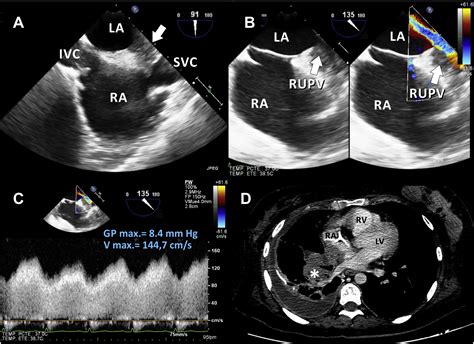

• Imaging Tests: Various imaging tests can help visualize the pulmonary veins and detect any narrowing or blockages. These tests may include:

Echocardiogram Uses sound waves to create images of the heart and pulmonary veins, assessing blood flow and detecting any narrowing.

Cardiac Catheterization Involves inserting a thin tube into the heart and pulmonary veins to measure pressure and blood flow, providing detailed information about the severity of stenosis.